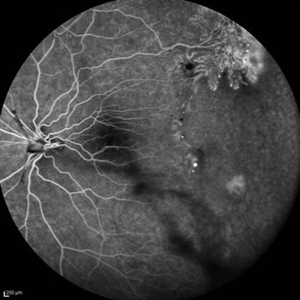

Behcet's Disease Behcet's DiseaseMar 13 2013 by Hamid Ahmadieh, MD Wide field FA of the left eye of a 23-year-old man with retinal vasculitis due to Behcet's disease . Photographer: Solmaz Shahmohammadi , Negah Eye Center, Tehran Imaging device: Heidelberg Spectralis Condition/keywords: retinal vasculitis